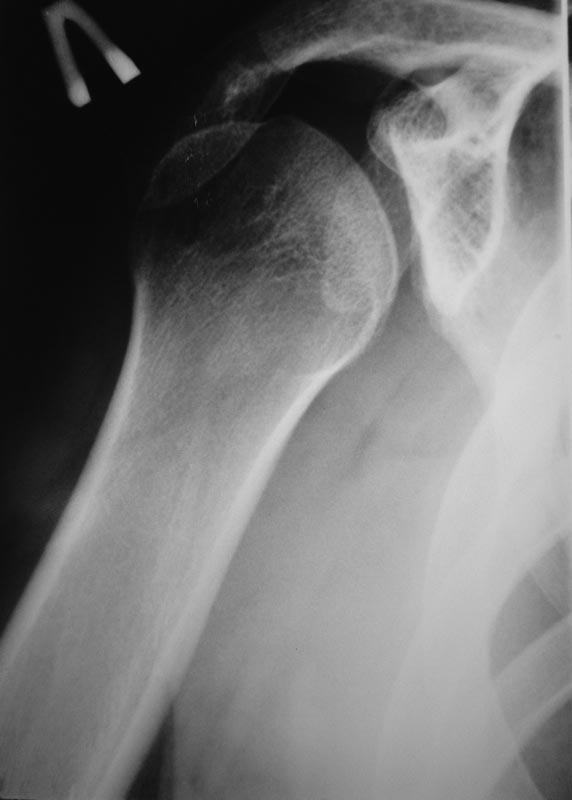

Уважаемые коллеги!Требуется ваша помощь. На консультацию обратился пациент 30 лет с жалобами на ограничение активных движений в левом плечевом суставе.

Пассивные – в полном объеме. Со слов – имела место некая родовая травма. К тому же отмечается незначительный дефицит иннервации n.radialis (снижение «силы» разгибателей-сгибателей в кистевом суставе и отведения 1 пальца; неврологи никакого специфичного лечения не назначают). Также имеется контрактура локтевого сустава: сгибание в полном объеме, разгибание 150 градусов, супинация в пределах 7 градусов. Функция конечности в принципе устраивает. Скелетных травм в анамнезе нет. Вопрос: есть ли смысл заниматься какими-либо реконструкциям на плечевом суставе и как можно улучшить функцию скомпрометированных суставов? Заранее всем благодарен